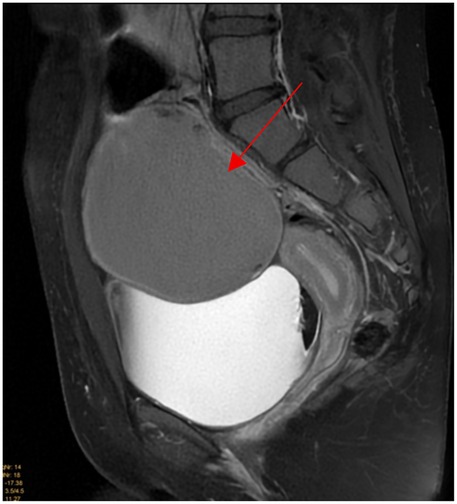

Pelvic ultrasound identified a large, well-defined, predominantly cystic mass arising from the right ovary, with internal septations and echogenic components suggestive of fat content (Figure 1). MRI of the pelvis confirmed a complex multilocular cystic lesion, measuring approximately 8–9 cm (Figure 2). No solid enhancing nodules or invasive features were seen. There was no evidence of pelvic lymphadenopathy or bone marrow infiltration.

Figure 1. Transabdominal ultrasound of the right ovary (RT OV) demonstrates homogeneous hypoechoic cystic adnexal mass without internal increased vascularity (red arrow).